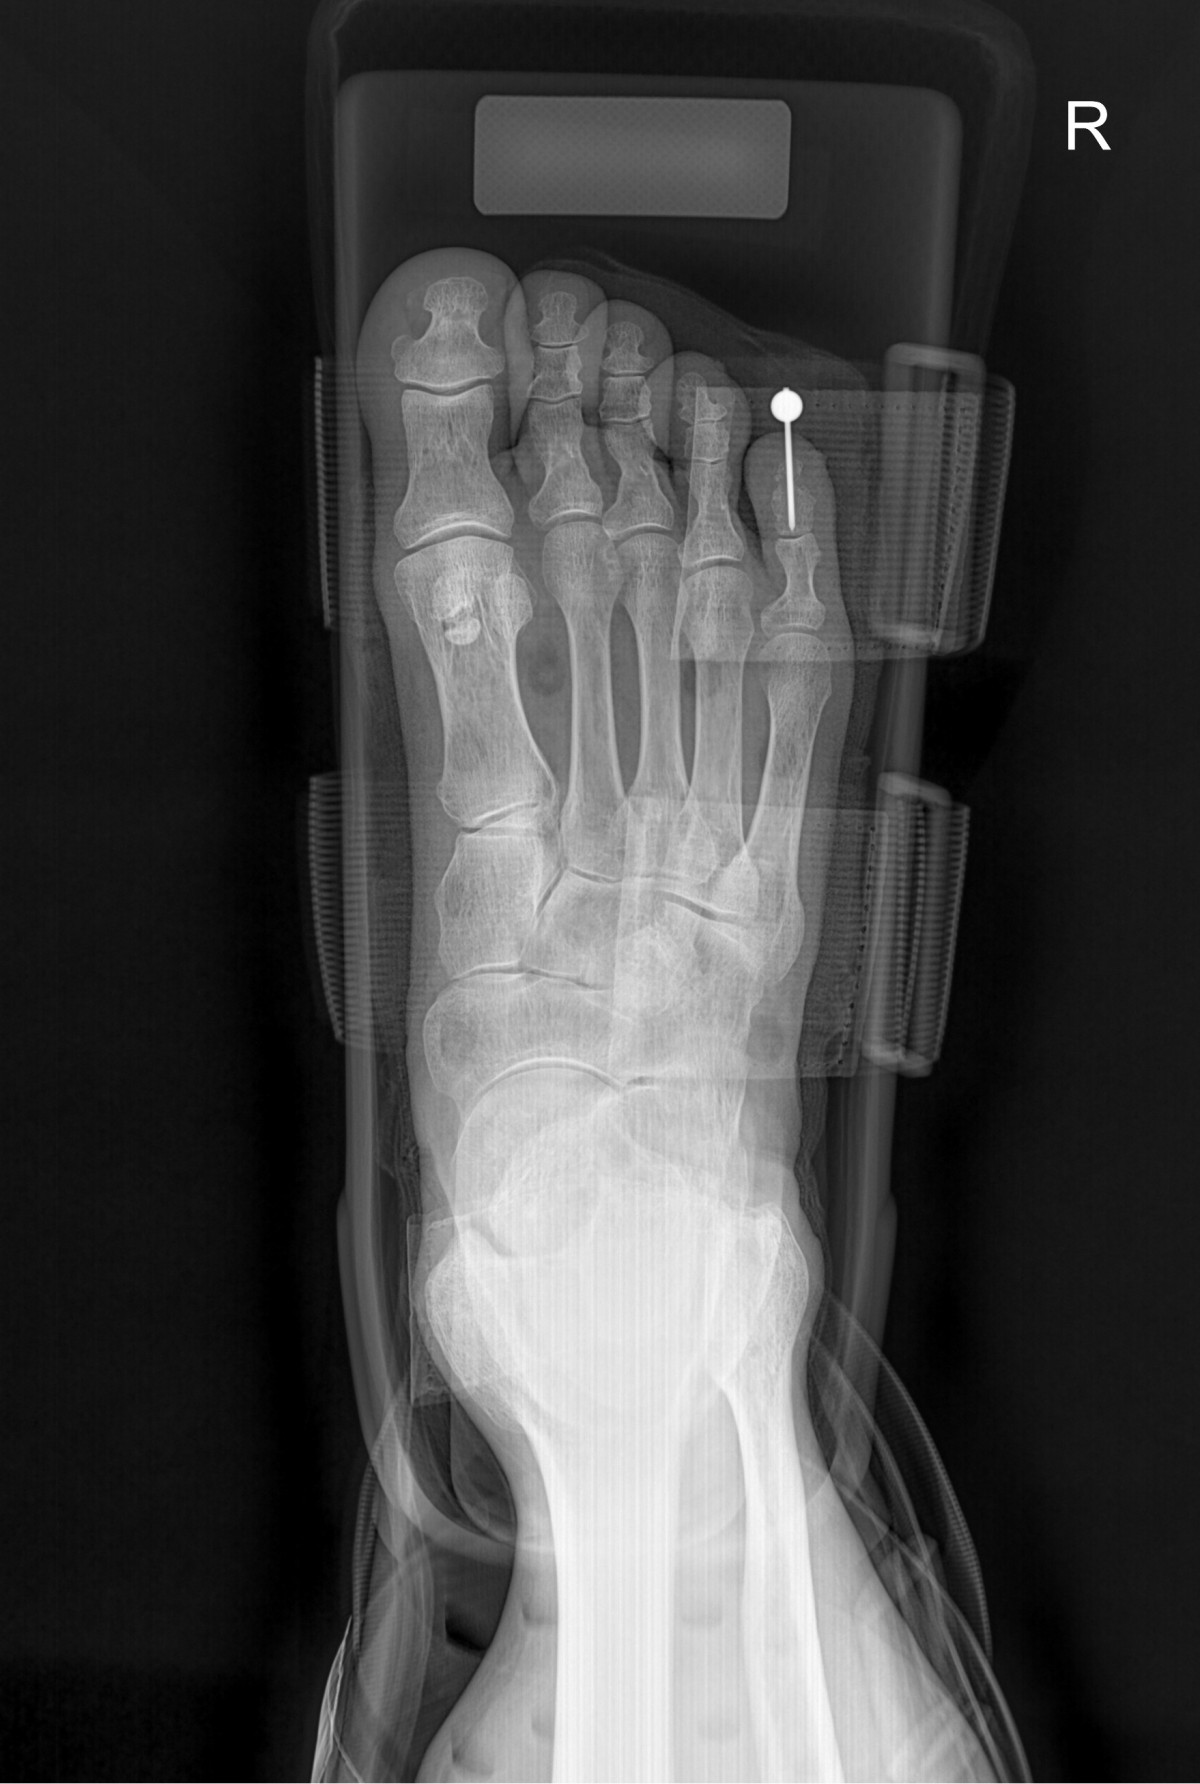

이재상원장님 발가락 골절 수술 김용O 환자

dae765e4d9ac96aee867c9d6292d8784_1758003546_4658.jpg